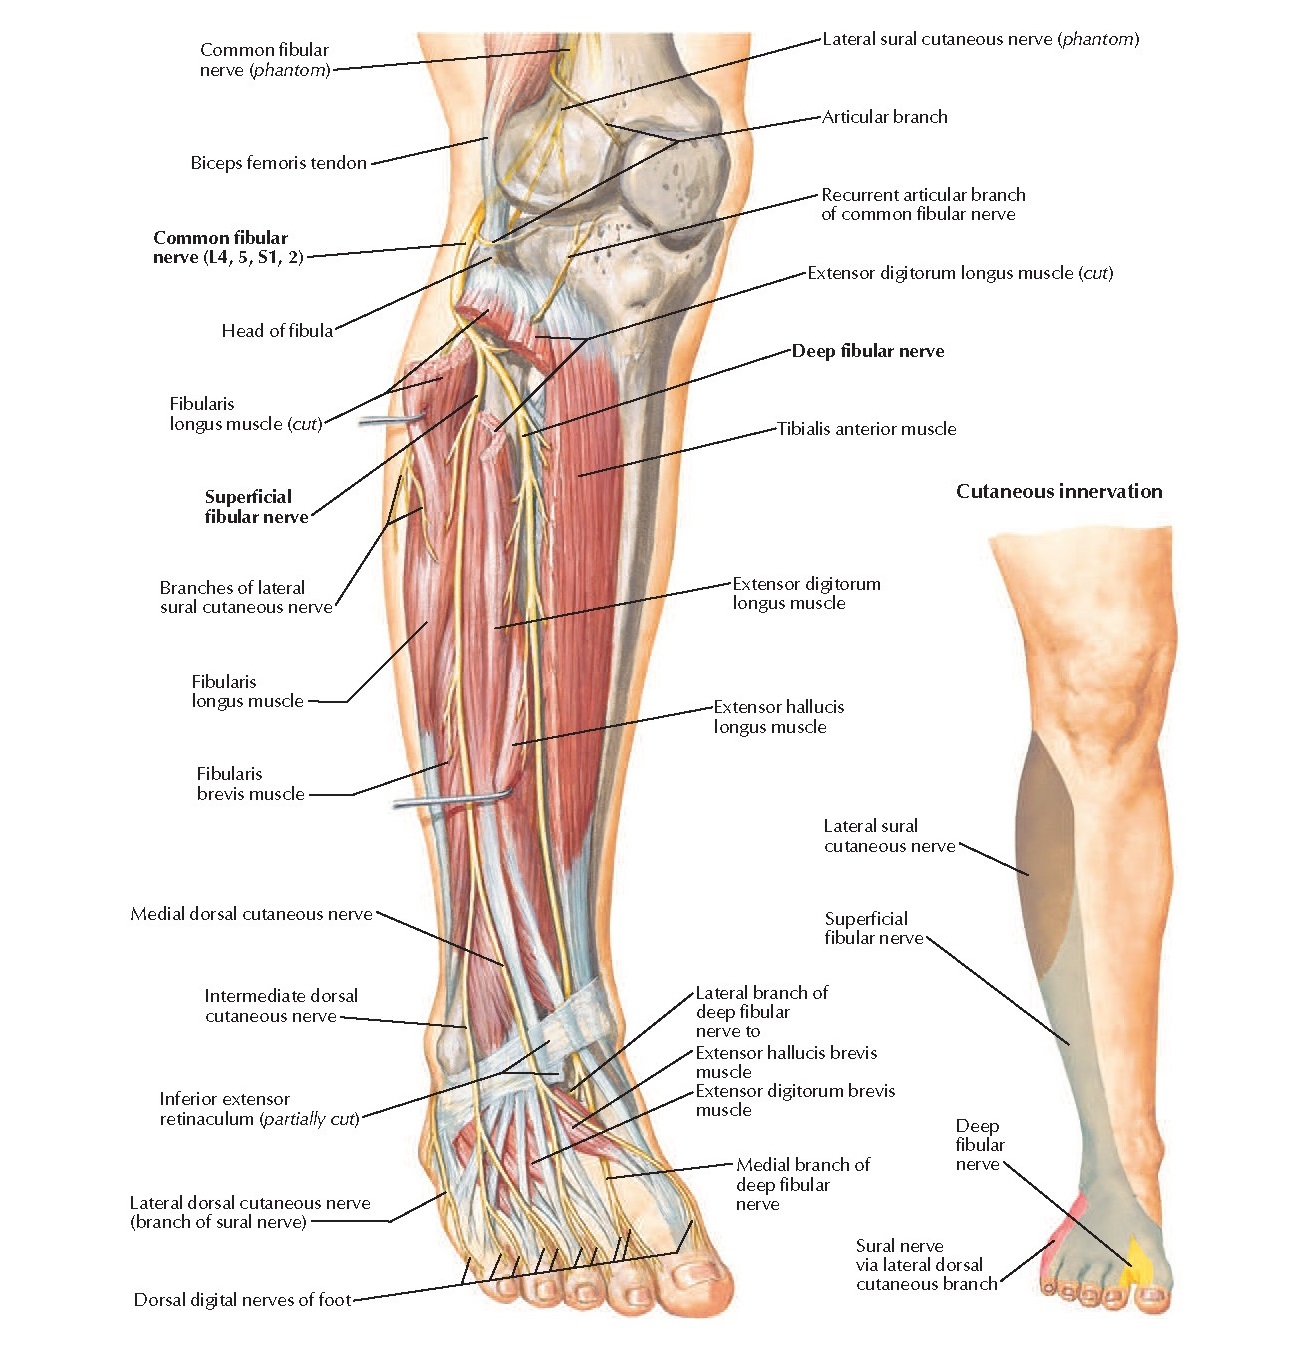

Common Fibular Nerve Anatomy – pediagenosis

ANATOMY 11 – LEG/ANKLE JOINT at Nanyang Polytechnic – StudyBlue

Nerves Leg Diagram – koibana.info | Nerves in leg, Muscle anatomy …